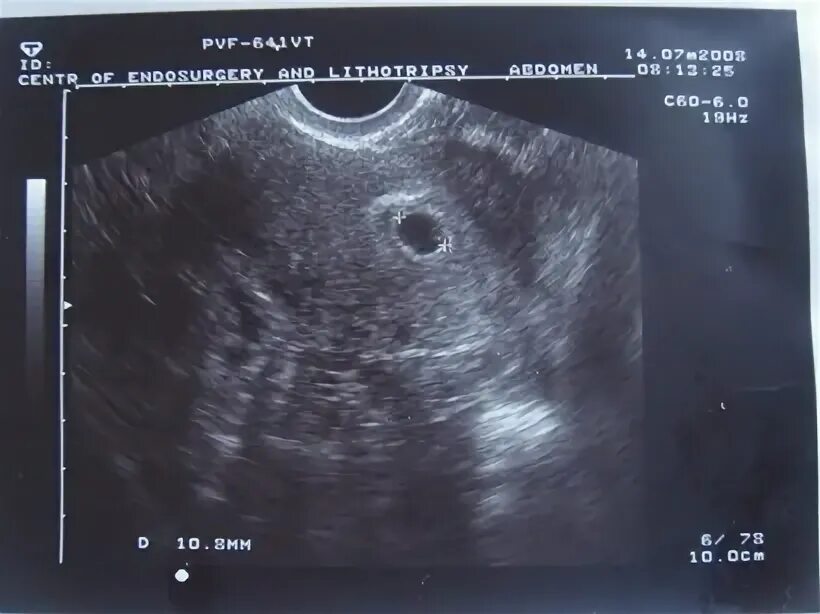

Беременна 2 недели срок